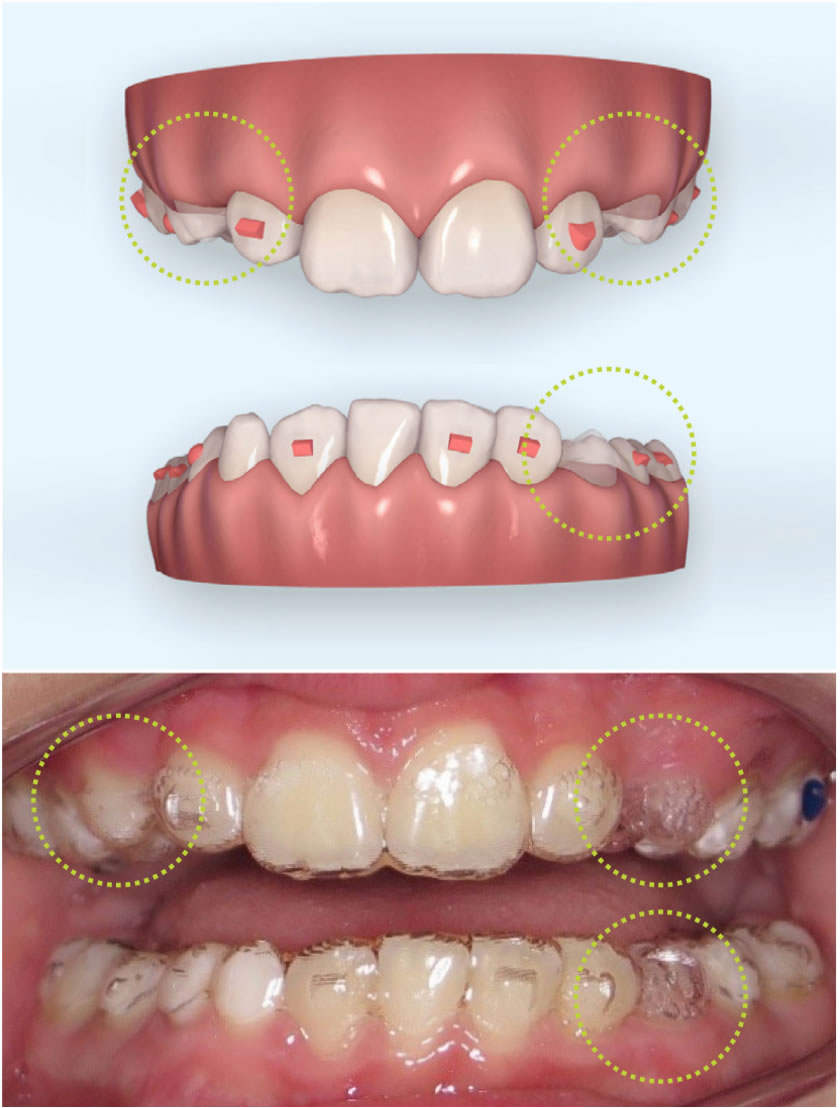

Invisalign First – Ortodontia Infantil com Conforto e Precisão

O Invisalign First é o sistema de alinhadores transparentes desenvolvido especialmente para crianças em fase de crescimento. Ele corrige problemas de mordida e alinhamento de forma confortável, removível e praticamente invisível, tornando o tratamento muito mais fácil para os pequenos e para os pais.

5. O Invisalign First realmente consegue expandir a arcada dentária?

Sim. Os alinhadores do Invisalign First são capazes de realizar movimentos de expansão, criando espaço para os dentes permanentes nascerem de forma adequada, quando indicado pelo ortodontista.